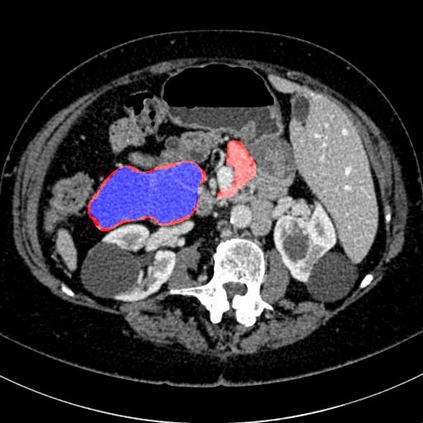

In this paper, we adopt 3D Convolutional Neural Networks to segment volumetric medical images. Although deep neural networks have been proven to be very effective on many 2D vision tasks, it is still challenging to apply them to 3D tasks due to the limited amount of annotated 3D data and limited computational resources. We propose a novel 3D-based coarse-to-fine framework to effectively and efficiently tackle these challenges. The proposed 3D-based framework outperforms the 2D counterpart to a large margin since it can leverage the rich spatial infor- mation along all three axes. We conduct experiments on two datasets which include healthy and pathological pancreases respectively, and achieve the current state-of-the-art in terms of Dice-S{\o}rensen Coefficient (DSC). On the NIH pancreas segmentation dataset, we outperform the previous best by an average of over 2%, and the worst case is improved by 7% to reach almost 70%, which indicates the reliability of our framework in clinical applications.